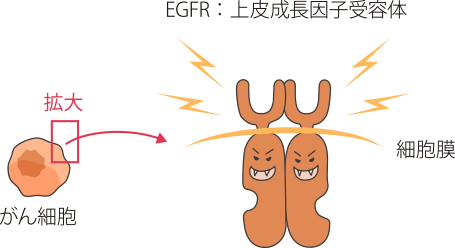

EGFRは、がん細胞が増殖するのに必要な信号を細胞内に伝えるタンパク質で、がん細胞の表面にたくさん発現していることが多く、このタンパク質からの信号が細胞内に伝わるとがん細胞が増殖します。

非小細胞肺がんの細胞の表面にはEGFR(上皮成長因子受容体)と呼ばれるタンパク質がたくさん発現しており、このEGFRは、外部から刺激を受けると、がん細胞が増え続ける(増殖)のに必要な信号を細胞内に伝える役割を担っています。

非小細胞肺がんにはこのEGFRを構成している遺伝子の一部(チロシンキナーゼ部位)に変異が認められる腫瘍があることがわかっています。

変異の中にはEGFRのスイッチを常時ONにして、がん細胞の増殖を促すものもあります。

EGFR遺伝子変異は、日本人の非小細胞肺がんの患者さん全体の30〜40%に認められます。欧米人よりも日本人などのアジア系の人種、男性よりも女性、タバコを吸う人よりも吸わない人に多く、非小細胞肺がんの中でも腺がんの患者さんに多いことなどがわかっています。

肺がんの治療薬であるEGFRチロシンキナーゼ阻害薬(EGFR-TKI)は、EGFR遺伝子変異のある患者さんで効果の高い薬剤といわれています。また、非小細胞肺がんの扁平上皮がんでは、EGFR遺伝子変異の発現頻度がとても低いことがわかっています。このため、扁平上皮がん以外の組織型の非小細胞肺がん患者さんは、薬物療法を開始する前にEGFR遺伝子変異検査をおこない、陽性の場合にEGFR-TKIを使うことが推奨されています。